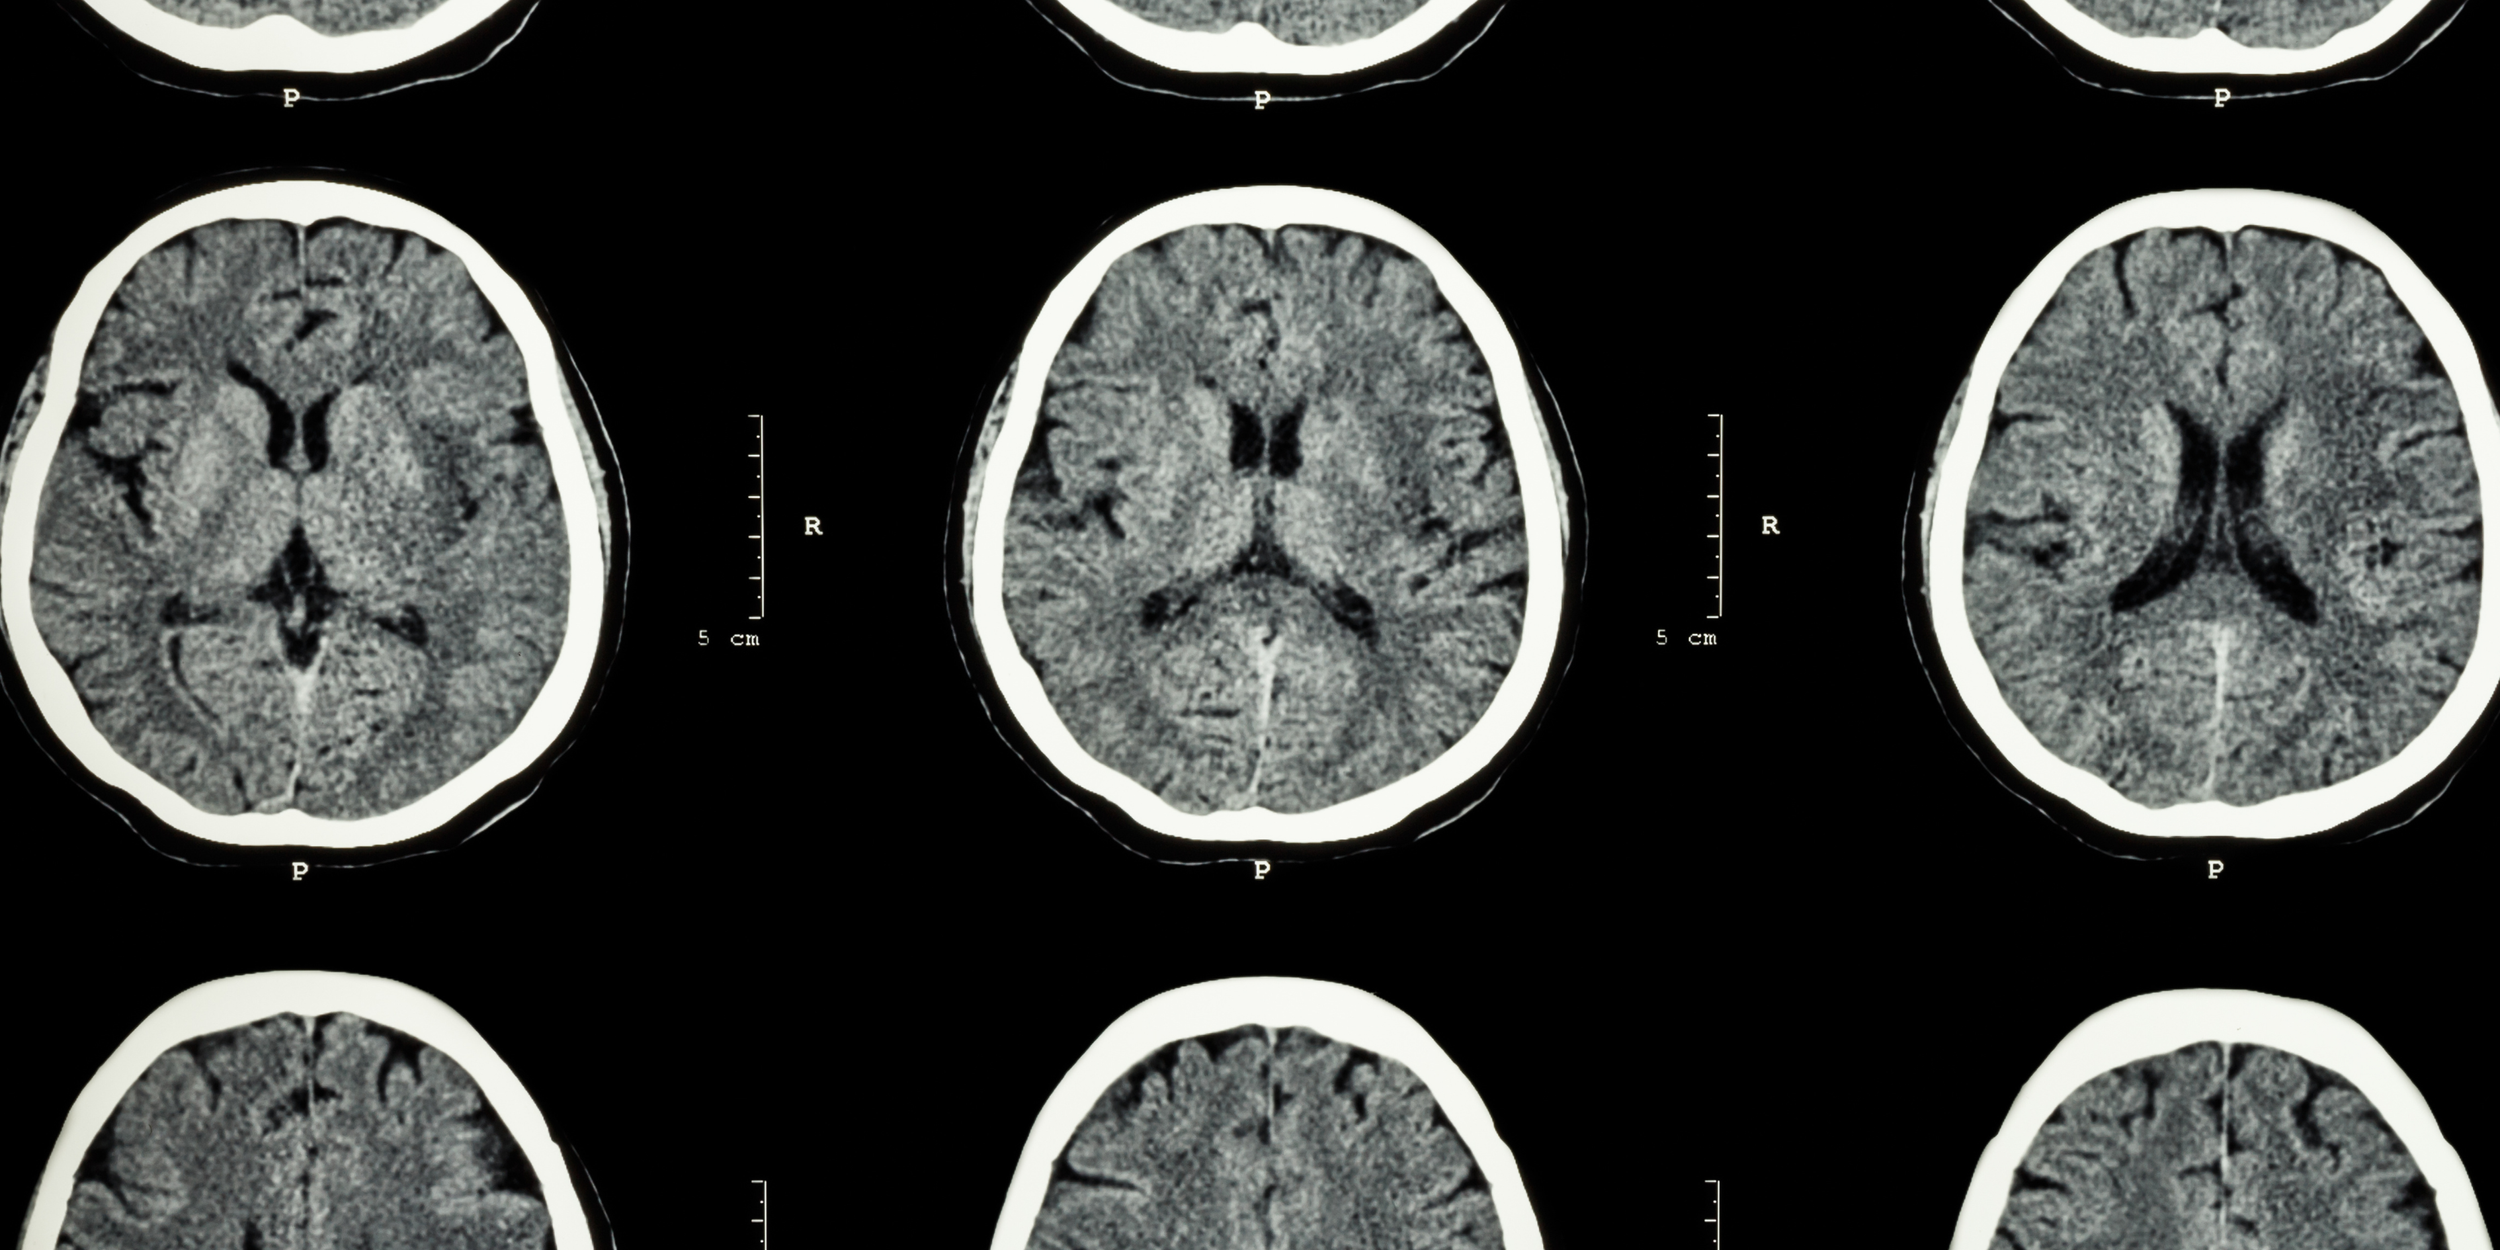

When we’re triggered, our amygdala — the brain’s built-in alarm system — takes charge. It releases stress hormones like cortisol and adrenaline, preparing the body to fight, flee, or freeze (LeDoux, 2000).

Meanwhile, the prefrontal cortex, which governs decision-making and self-control, temporarily goes offline. Under stress, communication between the prefrontal cortex and amygdala weakens, making us more reactive and less reflective (Arnsten, 2009).

A study in Frontiers in Psychology found that consistent emotional regulation practices improve mood stability, reduce anxiety, and enhance resilience (Gross, 2015). Similarly, mindfulness and self-awareness exercises have been shown to increase gray matter density in brain regions responsible for emotional balance (Hölzel et al., 2011).